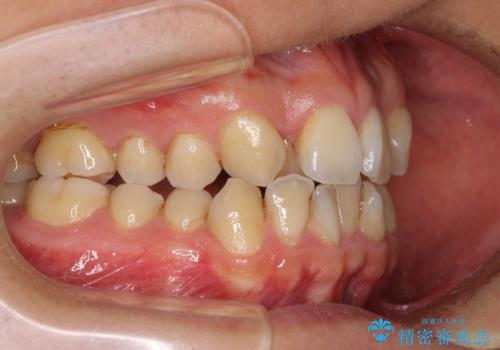

上顎の左右側切歯(前から2番目)が裏側に隠れいてる状態で、咬み合わせや清掃性に大きな問題が認められました。

下顎の歯列全体が右側にずれているため、右下のみ第二小臼歯を抜歯し、上顎は補助装置を使用して、極力上下の正中を合う位置にて咬み合わせを改善するようにしました。

元の歯列が想像できないほど、きれいな歯列に整えることができました。